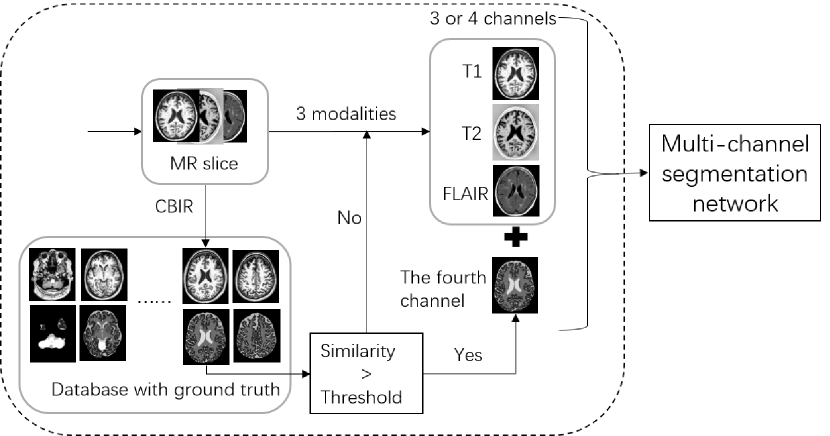

Achieving similar image with CBIR. We use CBIR to achieve the best similar image and use its ground truth as the fourth channel of the input. Image retrieval based on CBIR technology: Firstly, the features of the image in the database are extracted, and then the features of the query image are matched with the features of the images in the database, and finally the matched images are obtained. Through CBIR, we solve the problem of needing ground truth, which is concise to achieve. To do this, we first use CBIR to retrieve the best similar image to the test data, and then we register the two images and calculate the similarity of the images after registration. If the similarity is greater than a certain threshold, we will use its ground truth as the fourth channel of the network input (Figure 2), otherwise we will use the original three channels network.

Refer to caption

Figure 2: We use CBIR to match the most similar image in the database, if the obtained image’s similarity is larger than the threshold then its ground truth is used as the input of the fourth channel, otherwise we will use the original three channels network.